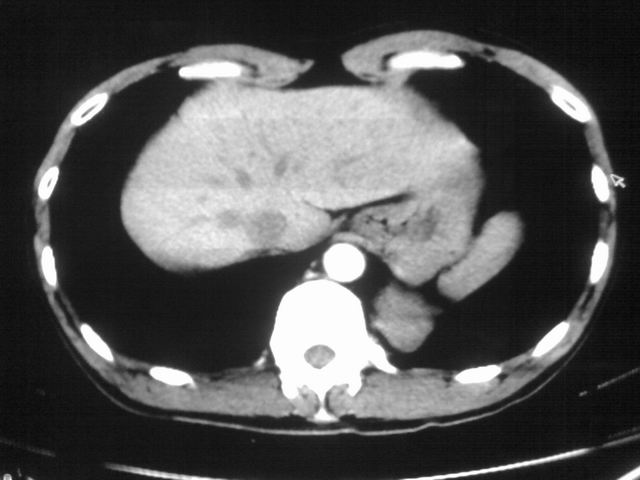

以下是引用苯小孩在2007-4-24 19:46:00的发言:[br]左下肺内侧基底段,见类圆形病灶,边缘清晰光滑.强化后轻中度强化.<平扫第4层面似有从腹主动脉相连血管影,可惜强化扫描这层没有抓住>考虑:左下肺隔离症.建议dsa或薄层强化重建观察.

以下是引用同在2007-4-24 20:11:00的发言:[br]考虑肺隔离症